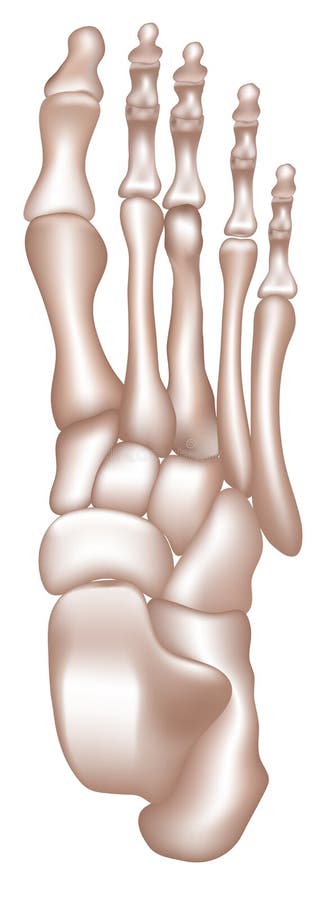

Келлера 4

Келлера 4 115 фото